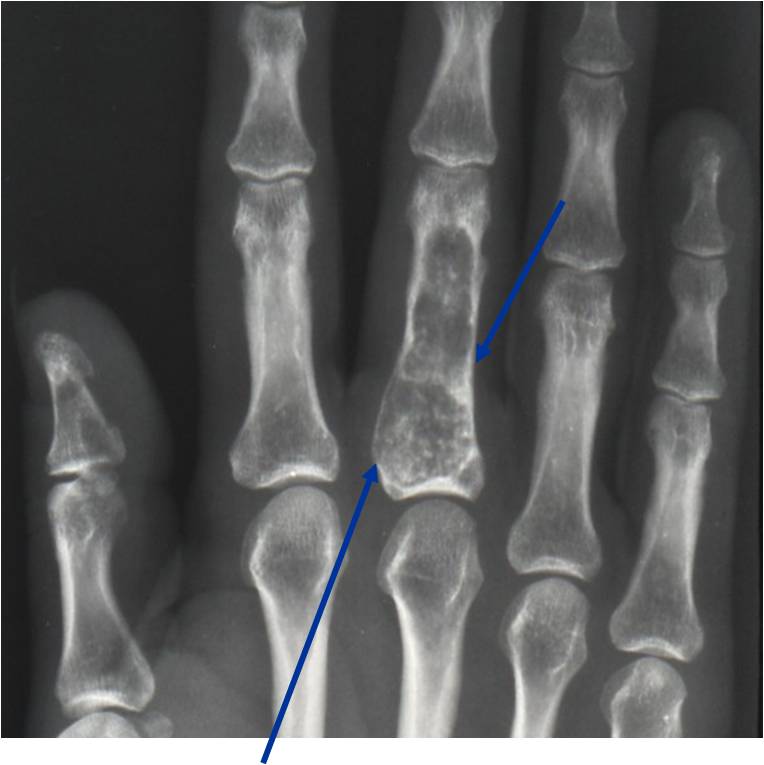

- 50% involve hands and feet (mostly phalanges)

- Localized, radiolucent defect usually with punctate calcifications

- Calcifications are typical but not always present

- Cortex may be scalloped and thinned in the phalanges

- Geographic lytic lesion

- Expansile remodeling with thinned cortex

- Chondroid matrix with calcifications in majority of tumors

- Digits: Impending or actual pathological fracture

- Intralesional curettage and bone graft or cement